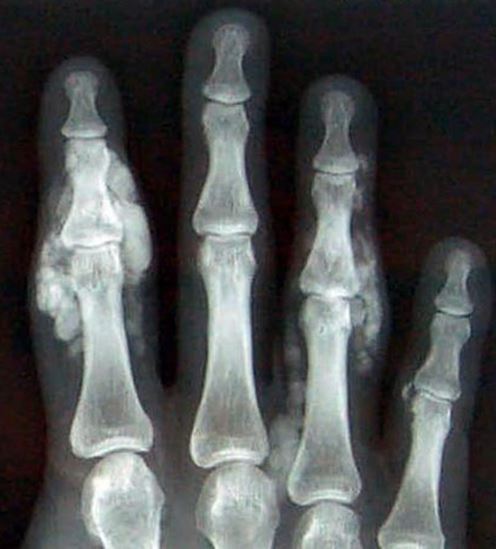

(1)1次以上的急性关节炎发作;(2)炎症表现在1天内达到高峰;(3)单关节炎发作;(4)患病关节皮肤呈暗红色;(5)第一跖关节疼痛或肿胀;(6)单侧发作累及第一跖趾关节;(7)单侧发作累及跗骨关节;(8)有可疑的痛风石;(9)高尿酸血症;(10)X线显示关节非对称性肿胀;(11)X线摄片示骨皮质下囊肿不伴有质侵蚀;(12)关节炎症发作期间关节液微生物培养阴性。

急性期的痛风应与急性风湿性关节炎、假性痛风、化脓性关节炎、外伤性关节炎 、淋病性关节炎相鉴别;慢性期的痛风应与慢性类风湿怀关节炎、银屑病性关节炎、结核变态反应性关节炎相鉴别。